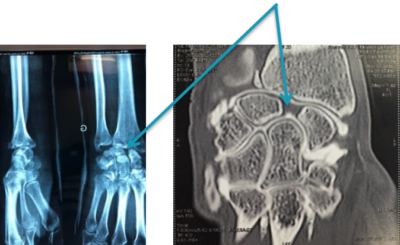

Ecart entre le scaphoïde et le semi-lunaire

Des radiographies simples du poignet seront toujours demandées. On recherchera des fractures associées et des écarts anormaux entre les différents os du carpe.

On peut demander une IRM pour dépister les ruptures ligamentaires. En cas de doute, un arthroscanner peut être réalisé. Un produit radio-opaque sera injecté dans le poignet et permettra de dépister les ruptures ligamentaires.

Fixation temporaire des broches

Dans les autres cas, il faudra envisager un traitement chirurgical ambulatoire (vous entrez et sortez de l’hôpital le même jour que votre intervention) sous anesthésie loco-régionale (seul le bras est endormi) afin de réparer le ligament abîmé. Le principe du traitement est de remplacer le ligament abîmé par une autre structure (ligamentoplastie ou capsulodèse) et de remettre en place les 2 os qui étaient maintenus par le ligament abîmé en les fixant temporairement par des broches qui seront laissées en place environ 8 semaines.